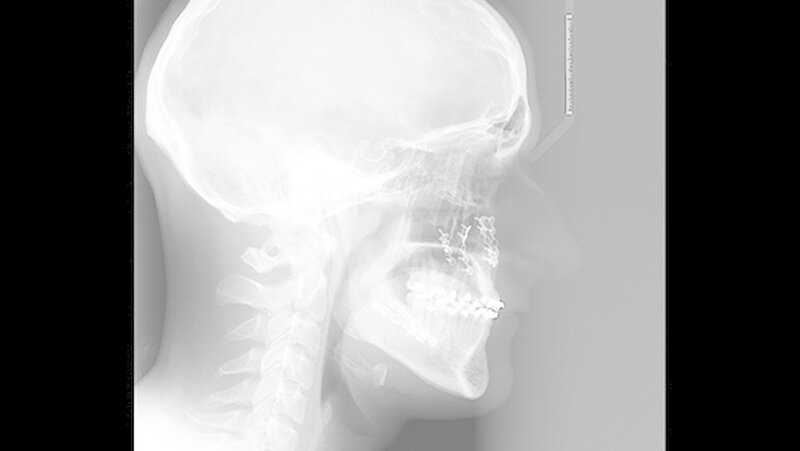

Die Abbildungen 1 und 2 zeigen die klinische Situation bei Erstvorstellung: Der Unterkiefer ist zu prominent. Der Oberkiefer und das Mittelgesicht liegen zurück. In der Front liegt ein umgekehrter Überbiss vor. Der Unterkiefer steht vor dem Oberkiefer. Das erschwert das Abbeißen und Kauen der Nahrung. Die Scans (siehe Abbildungen) dokumentieren, wie aufwendig die virtuelle Operationsplanung erfolgen musste.

Im Dezember 2014 führen die MKG-Chirurgen des Stuttgarter Katharinenhospitals die Umstellung des Ober- und Unterkiefers nach virtueller Chirurgie-Planung durch: Dabei trennen sie den Oberkiefer horizontal vom Gesichtsschädel ab (horizontale Osteotomie in der LeFort Ebene).

Hierzu wird von einem Schnitt im Mund der Oberkieferknochen freigelegt. Mit einer Säge kann ein gezielter Knochenschnitt erfolgen, und nach Präparation wird der Zahn tragende Abschnitt des Oberkiefers vom restlichen Gesichtsschädel gelöst.

Nun muss die Biss-Situation anhand des Computer gefertigten Biss-Schlüssels exakt eingestellt werden, bevor mit zwei Millimeter dicken Osteosyntheseplatten aus Titan der Knochen in der neuen Position mit Hilfe von Titanschrauben fixiert wird. Im Unterkiefer erfolgt die Schnittführung im Zahnfleisch hinter dem letzten Backenzahn beidseits. Nun wird der Unterkiefer mit spezieller Technik durchtrennt. Dies erlaubt eine Verschiebung der Zahn tragenden Basis vom Gelenk tragenden Knochenabschnitt des Unterkiefers.